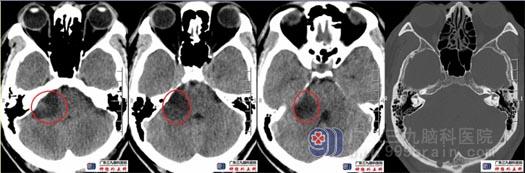

术后4小时复查头颅CT示局部未见出血,小脑半球已复胀,肿瘤切除满意。